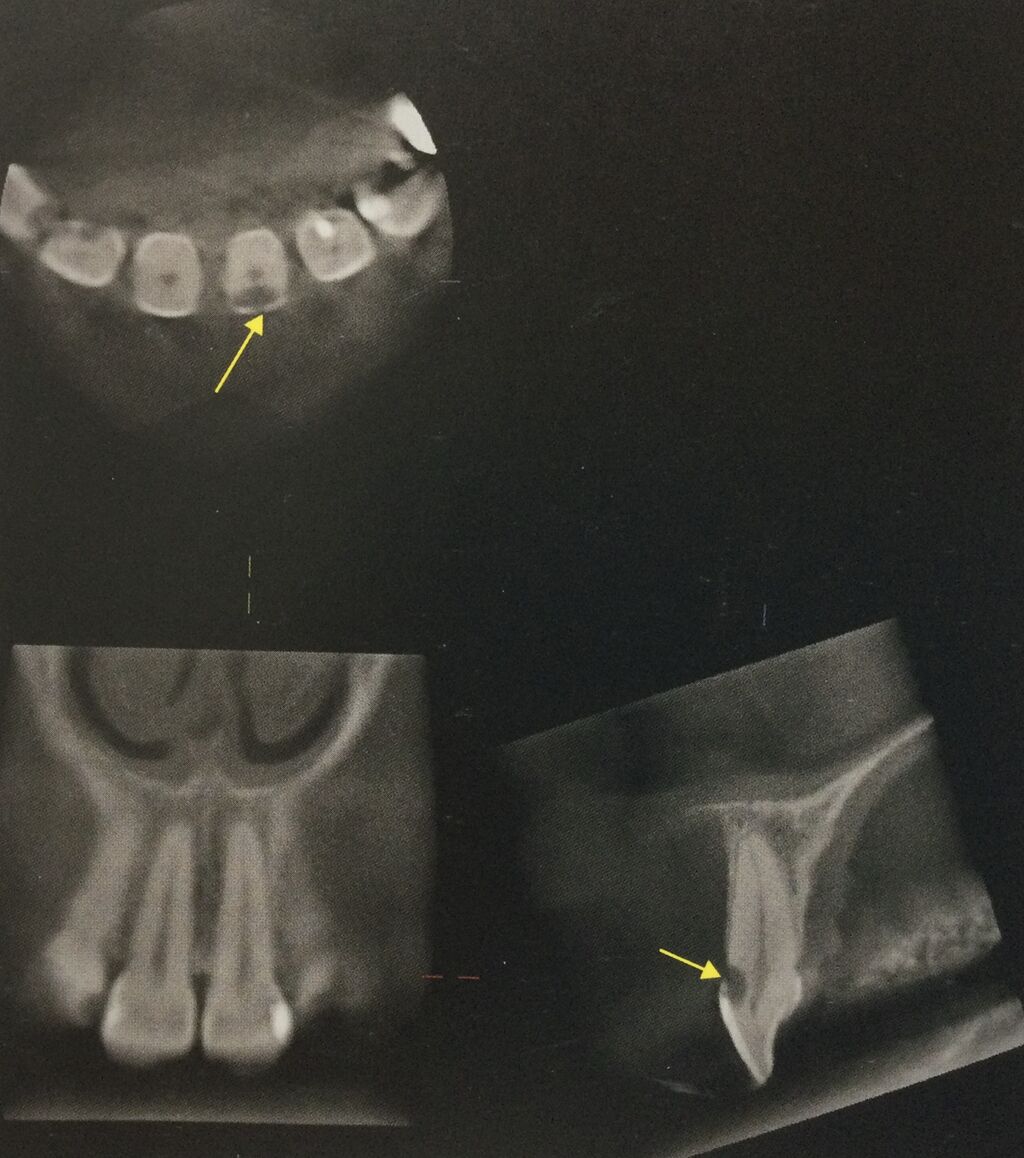

この歯では、

CTから分かることは?

歯の真ん中にある黒い部分が、歯の神経です。

溶けたカゲと神経がくっ付いていません。

この歯では詰めるだけの残った歯、象牙質が十分に残っていそうです。

病気、カゲの正確な位置が分かります。

骨との位置も良く分かります。